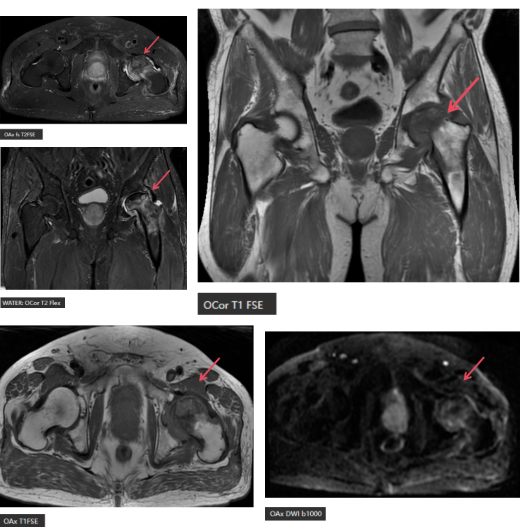

MR表现:左侧股骨头变扁,局部塌陷,骨质内见线状T1WI低信号,髋臼及股骨近端骨松质见片状T1WI低、T2WI压脂高信号,DWI高信号,周围滑膜增厚,邻近软组织肿胀,PD压脂信号增高,关节腔少量积液。

①早期发现:X光只能看到骨骼的形态变化,而股骨头坏死最早发生的是骨髓内的水肿和缺血,这些在X光上是看不见的。MRI能敏感地检测到骨髓水肿、坏死区与存活区的分界,比X光提前几个月甚至一两年发现病变。本例中的线状低信号、片状水肿,都是MRI的“专属发现”。

②精准分期:股骨头坏死的治疗与分期密切相关。MRI能清晰显示坏死的范围、有无塌陷、关节有无积液等,帮助医生判断是保守治疗(如药物、理疗、减重)还是手术治疗(如髓芯减压、植骨、人工髋关节置换)。

④多参数成像:MRI能通过不同序列反映组织的多种特性——T1WI看解剖结构,T2WI压脂看水肿,DWI看细胞密度...这些信息叠加在一起,让诊断更准确。

这位68岁的患者,虽然已经出现塌陷,但MRI的精准评估为后续治疗提供了清晰“地图”,让医生能准确判断病情、选择最合适的治疗方案。